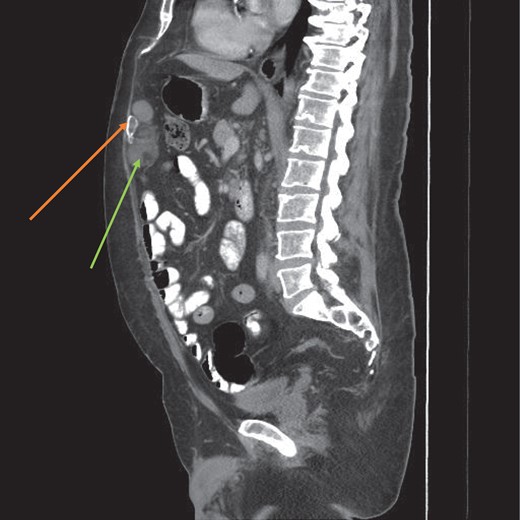

His medical history was significant for hypertension and alchoholism and both were well controlled. Radiological imaging included a computerized tomography (CT) scan which reported an internal hernia in the epigastrium (Figs 1 and 2). There were no radiological signs of bowel strangulation.

CT scan sagittal view of the myelolipoma (green arrow) with a calcified component (orange arrow).